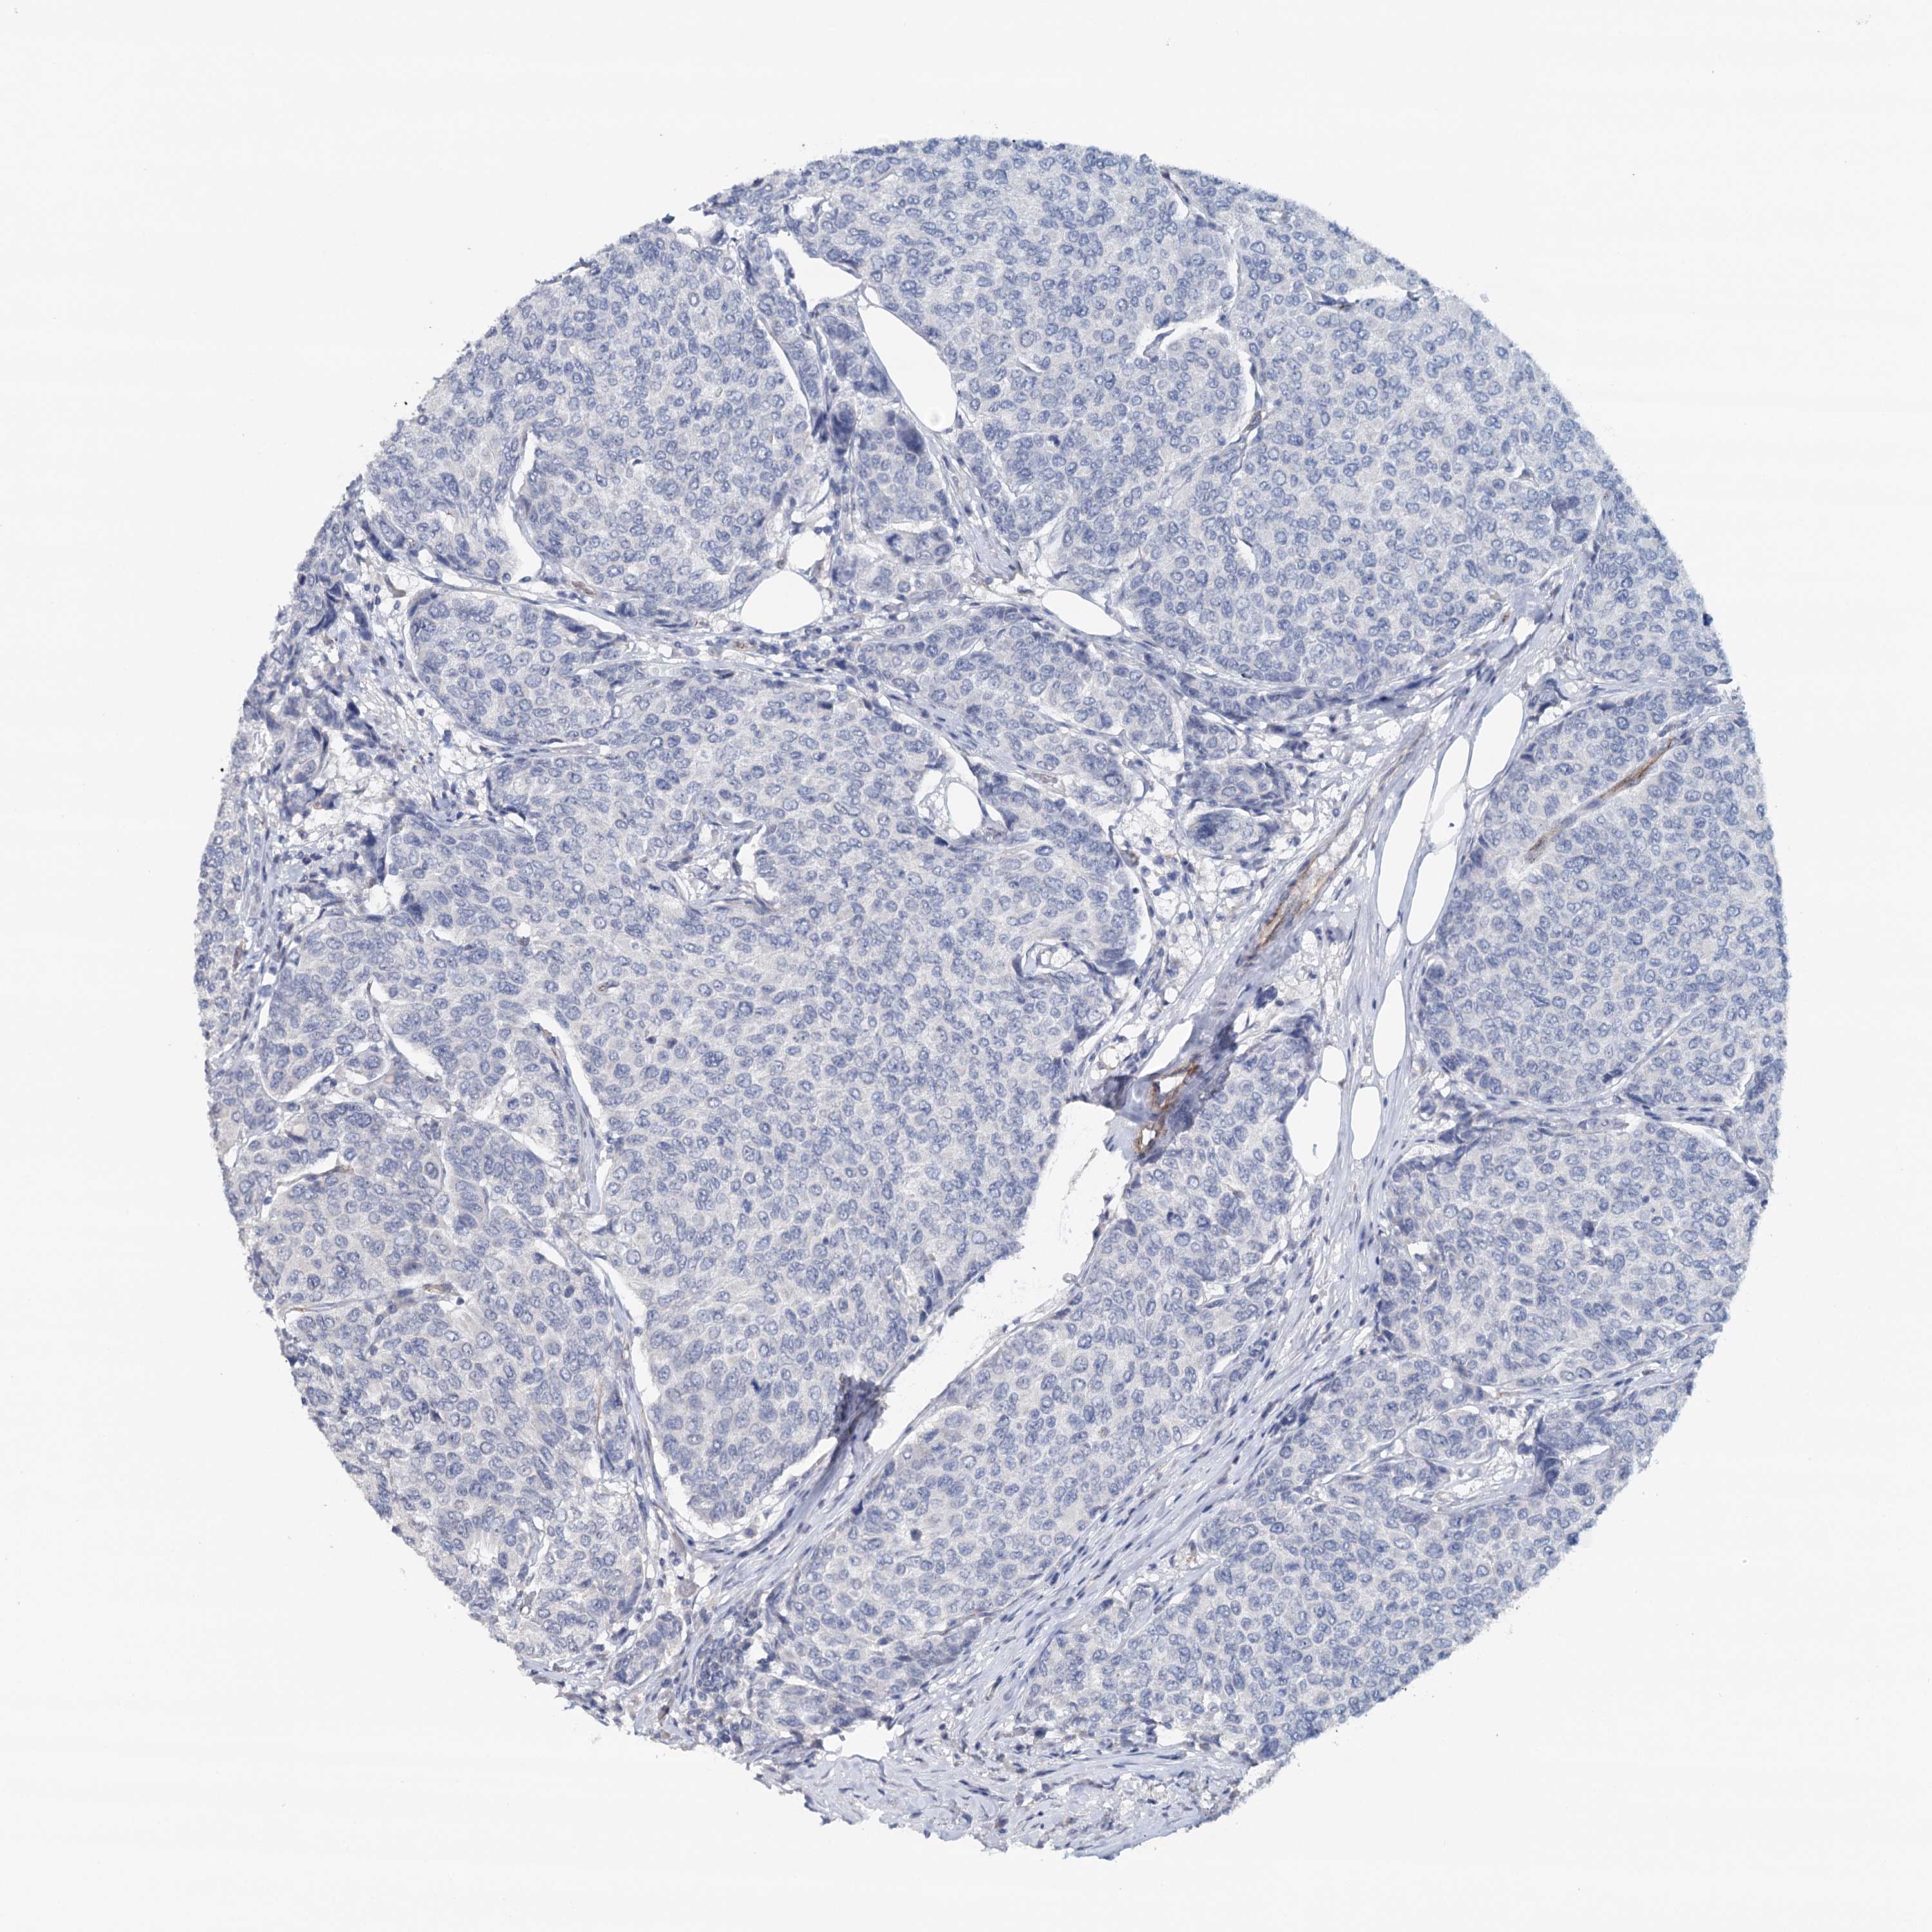

CANCER BREAST CANCER Show tissue menu

BRCA TCGA BRCA VALIDATION PROTEIN EXPRESSION